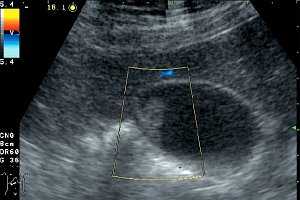

При использовании в 10 случаях допплеровских методов ни внутри полипа, ни в его ножке кровоток зарегистрировать не удалось (рис. 2). Дрожание полипов в виде пламени свечи, свидетельствующее об их тонкой ножке, вызывает движение расположенных рядом с полипом слоев желчи. В результате этого около полипа регистрируется цветовой сигнал.

![УЗИ. Холестериновый полип размером 22 мм, в режиме цветного допплеровского картирования кровоток не регистрируется]()

Рис. 2. Холестериновый полип размером 22 мм, в режиме цветного допплеровского картирования кровоток не регистрируется.